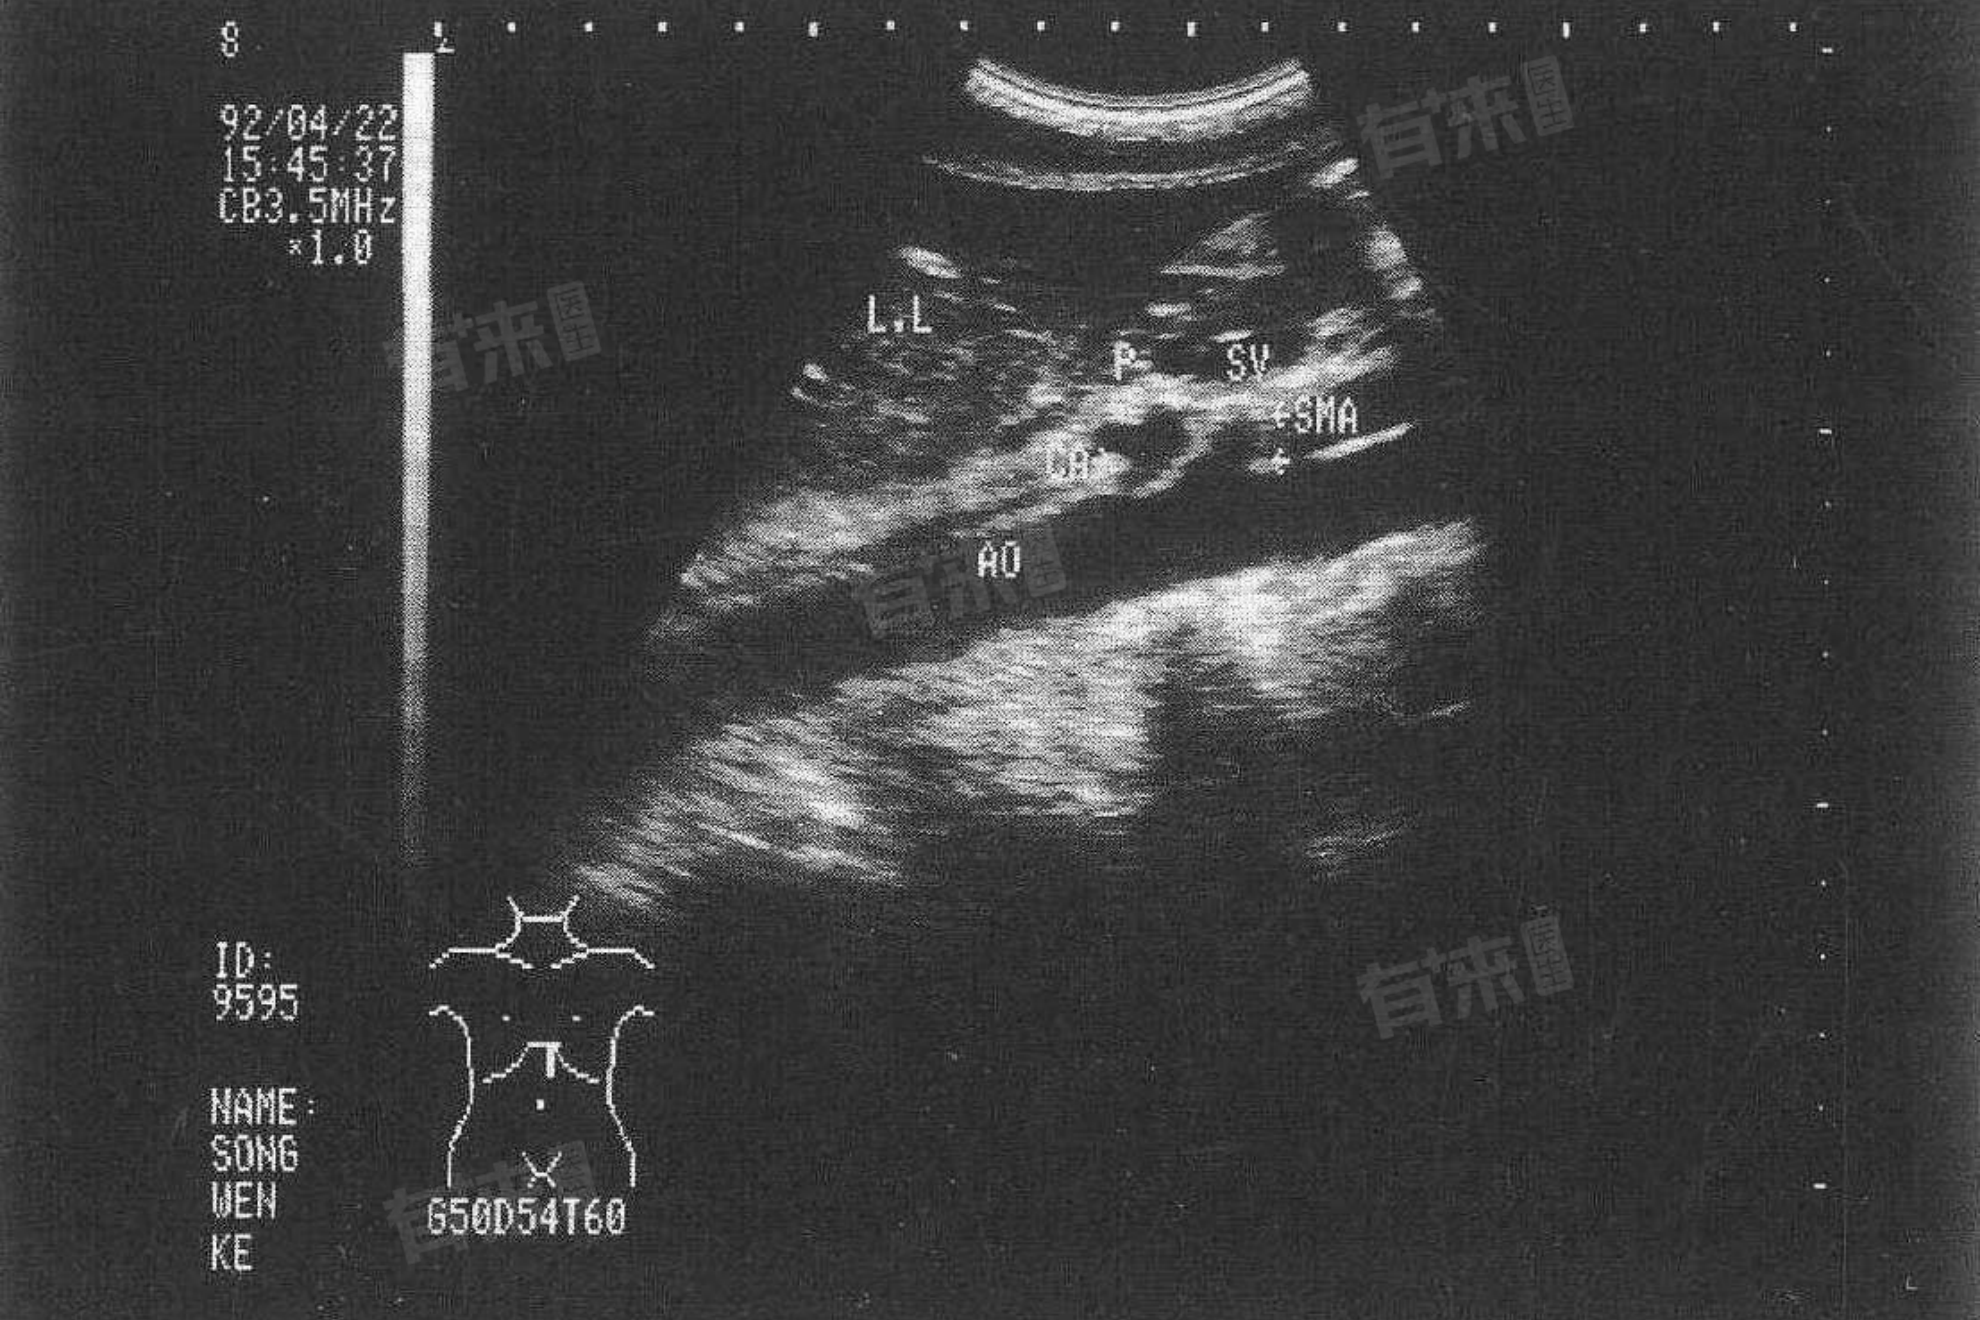

肝左叶钙化灶是指肝脏左侧叶部位出现了钙盐沉积的病灶,通常在B超或CT影像上表现为肝脏内出现强回声或高密度影像。是否严重,需要根据实际情况而定。

- 良性病变:大多数情况下,肝左叶钙化灶是良性病变,不会对身体健康造成明显的不良影响。这些钙化灶通常较小,数量较少或分布分散,对肝功能没有显著影响。

- 无需特殊治疗:对于良性且无症状的肝左叶钙化灶,通常不需要进行特殊治疗。患者只需定期进行B超或CT等影像学检查,以观察钙化灶的变化情况。

- 恶性病变的可能性:虽然肝左叶钙化灶大多数情况下是良性的,但也不能完全排除恶性病变的可能性。如果钙化灶数量较多、体积较大或分布密集,且伴有肝功能异常或临床症状,则可能需要进一步检查和治疗。然而,这种情况相对罕见。